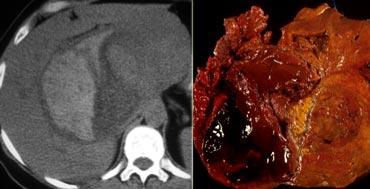

Tổn thương này chắc chắn có một số đặc điểm của u máu như ngấm thuốc dạng nốt trong thì động mạch và ngấm thuốc lấp đầy dần trong thì tĩnh mạch cửa và thì cân bằng.

Tuy nhiên, trong thì tĩnh mạch cửa, mức độ ngấm thuốc không sáng bằng mức độ ngấm thuốc của tĩnh mạch cửa.

Kết luận phải là tổn thương này không tương đương hồ máu ở tất cả các thì, do đó không thể là u máu.

Vì vậy, ngấm thuốc lấp đầy dần là một đặc điểm không đặc hiệu, có thể gặp trong nhiều tổn thương khác như di căn hoặc các khối u gan nguyên phát như ung thư biểu mô đường mật.

Sự ngấm thuốc thì muộn trong tổn thương này là do mô xơ trong ung thư biểu mô đường mật và là đặc điểm đặc trưng của các khối u này.